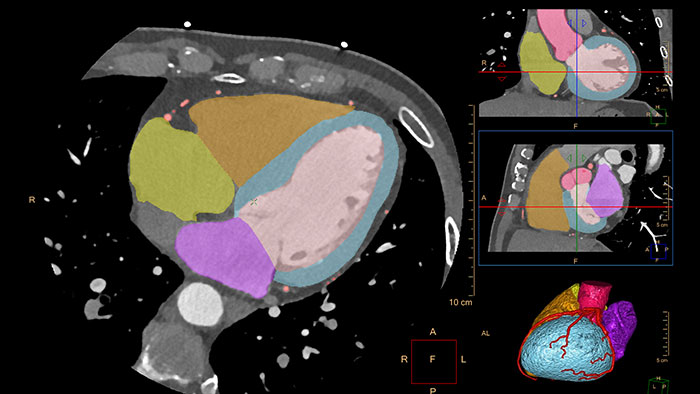

CT Comprehensive Cardiac Analysis (CCA)

Comprehensive cardiac analysis

Designed to assist the user in viewing, analyzing and quantifying dedicated Cardiac CT Angiograms, mainly for coronary arteries analysis on Coronaries CT Angiogram (CCTA) data.

Benefits

- Cardiac function measurements based on automatic 3D model-based whole-heart segmentation.

- Automatic extraction and visualization of the coronary tree.

- The user can edit and modify the segmentation and the derived parameters.